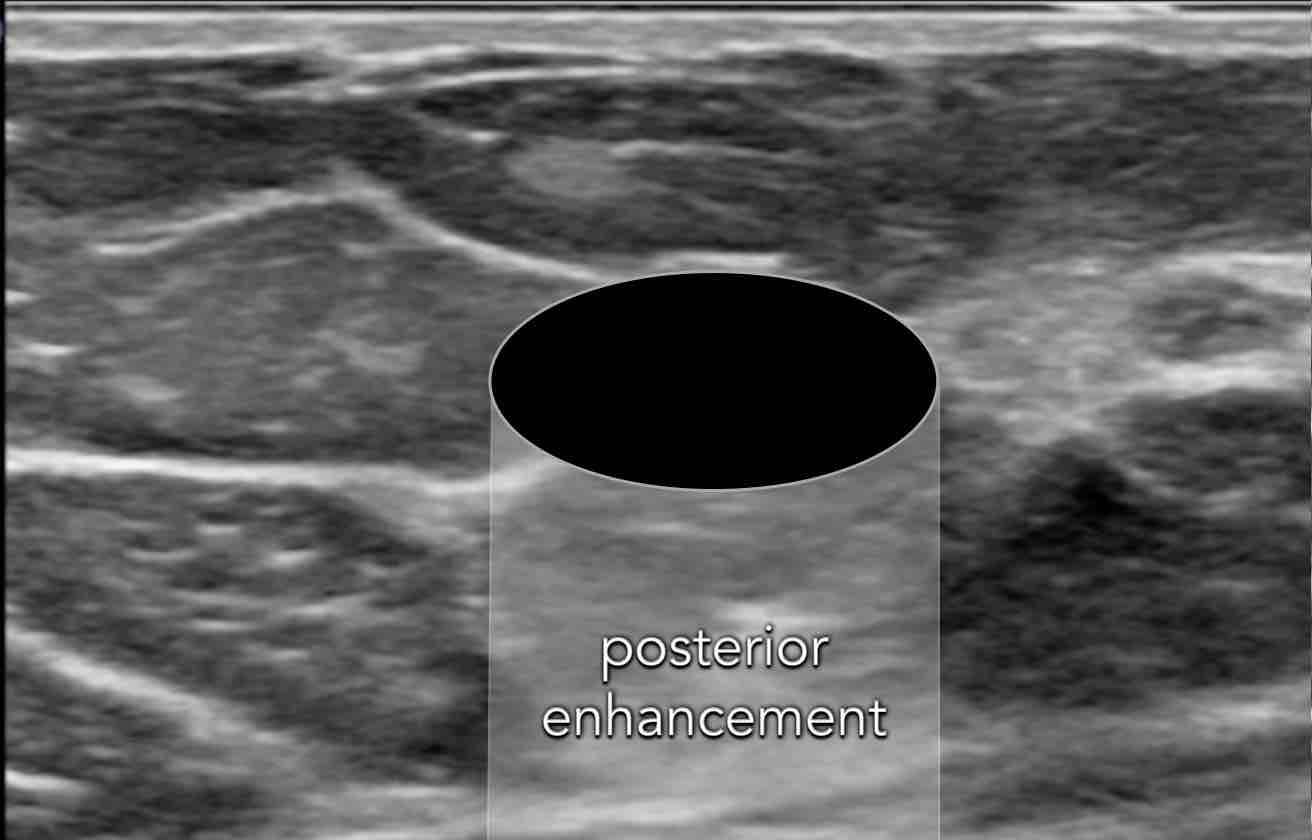

- Tăng âm phía sau

Phía sau nang thường có hiện tượng tăng âm, còn gọi là tăng âm phía sau, đề cập đến sự gia tăng các tín hiệu âm ở phía sâu sau nang, do dịch lỏng truyền âm rất tốt.

Cũng cần lưu ý hiện tượng tăng âm phía sau (posterior enhancement) — đây là dấu hiệu cho thấy cấu trúc này chứa dịch.